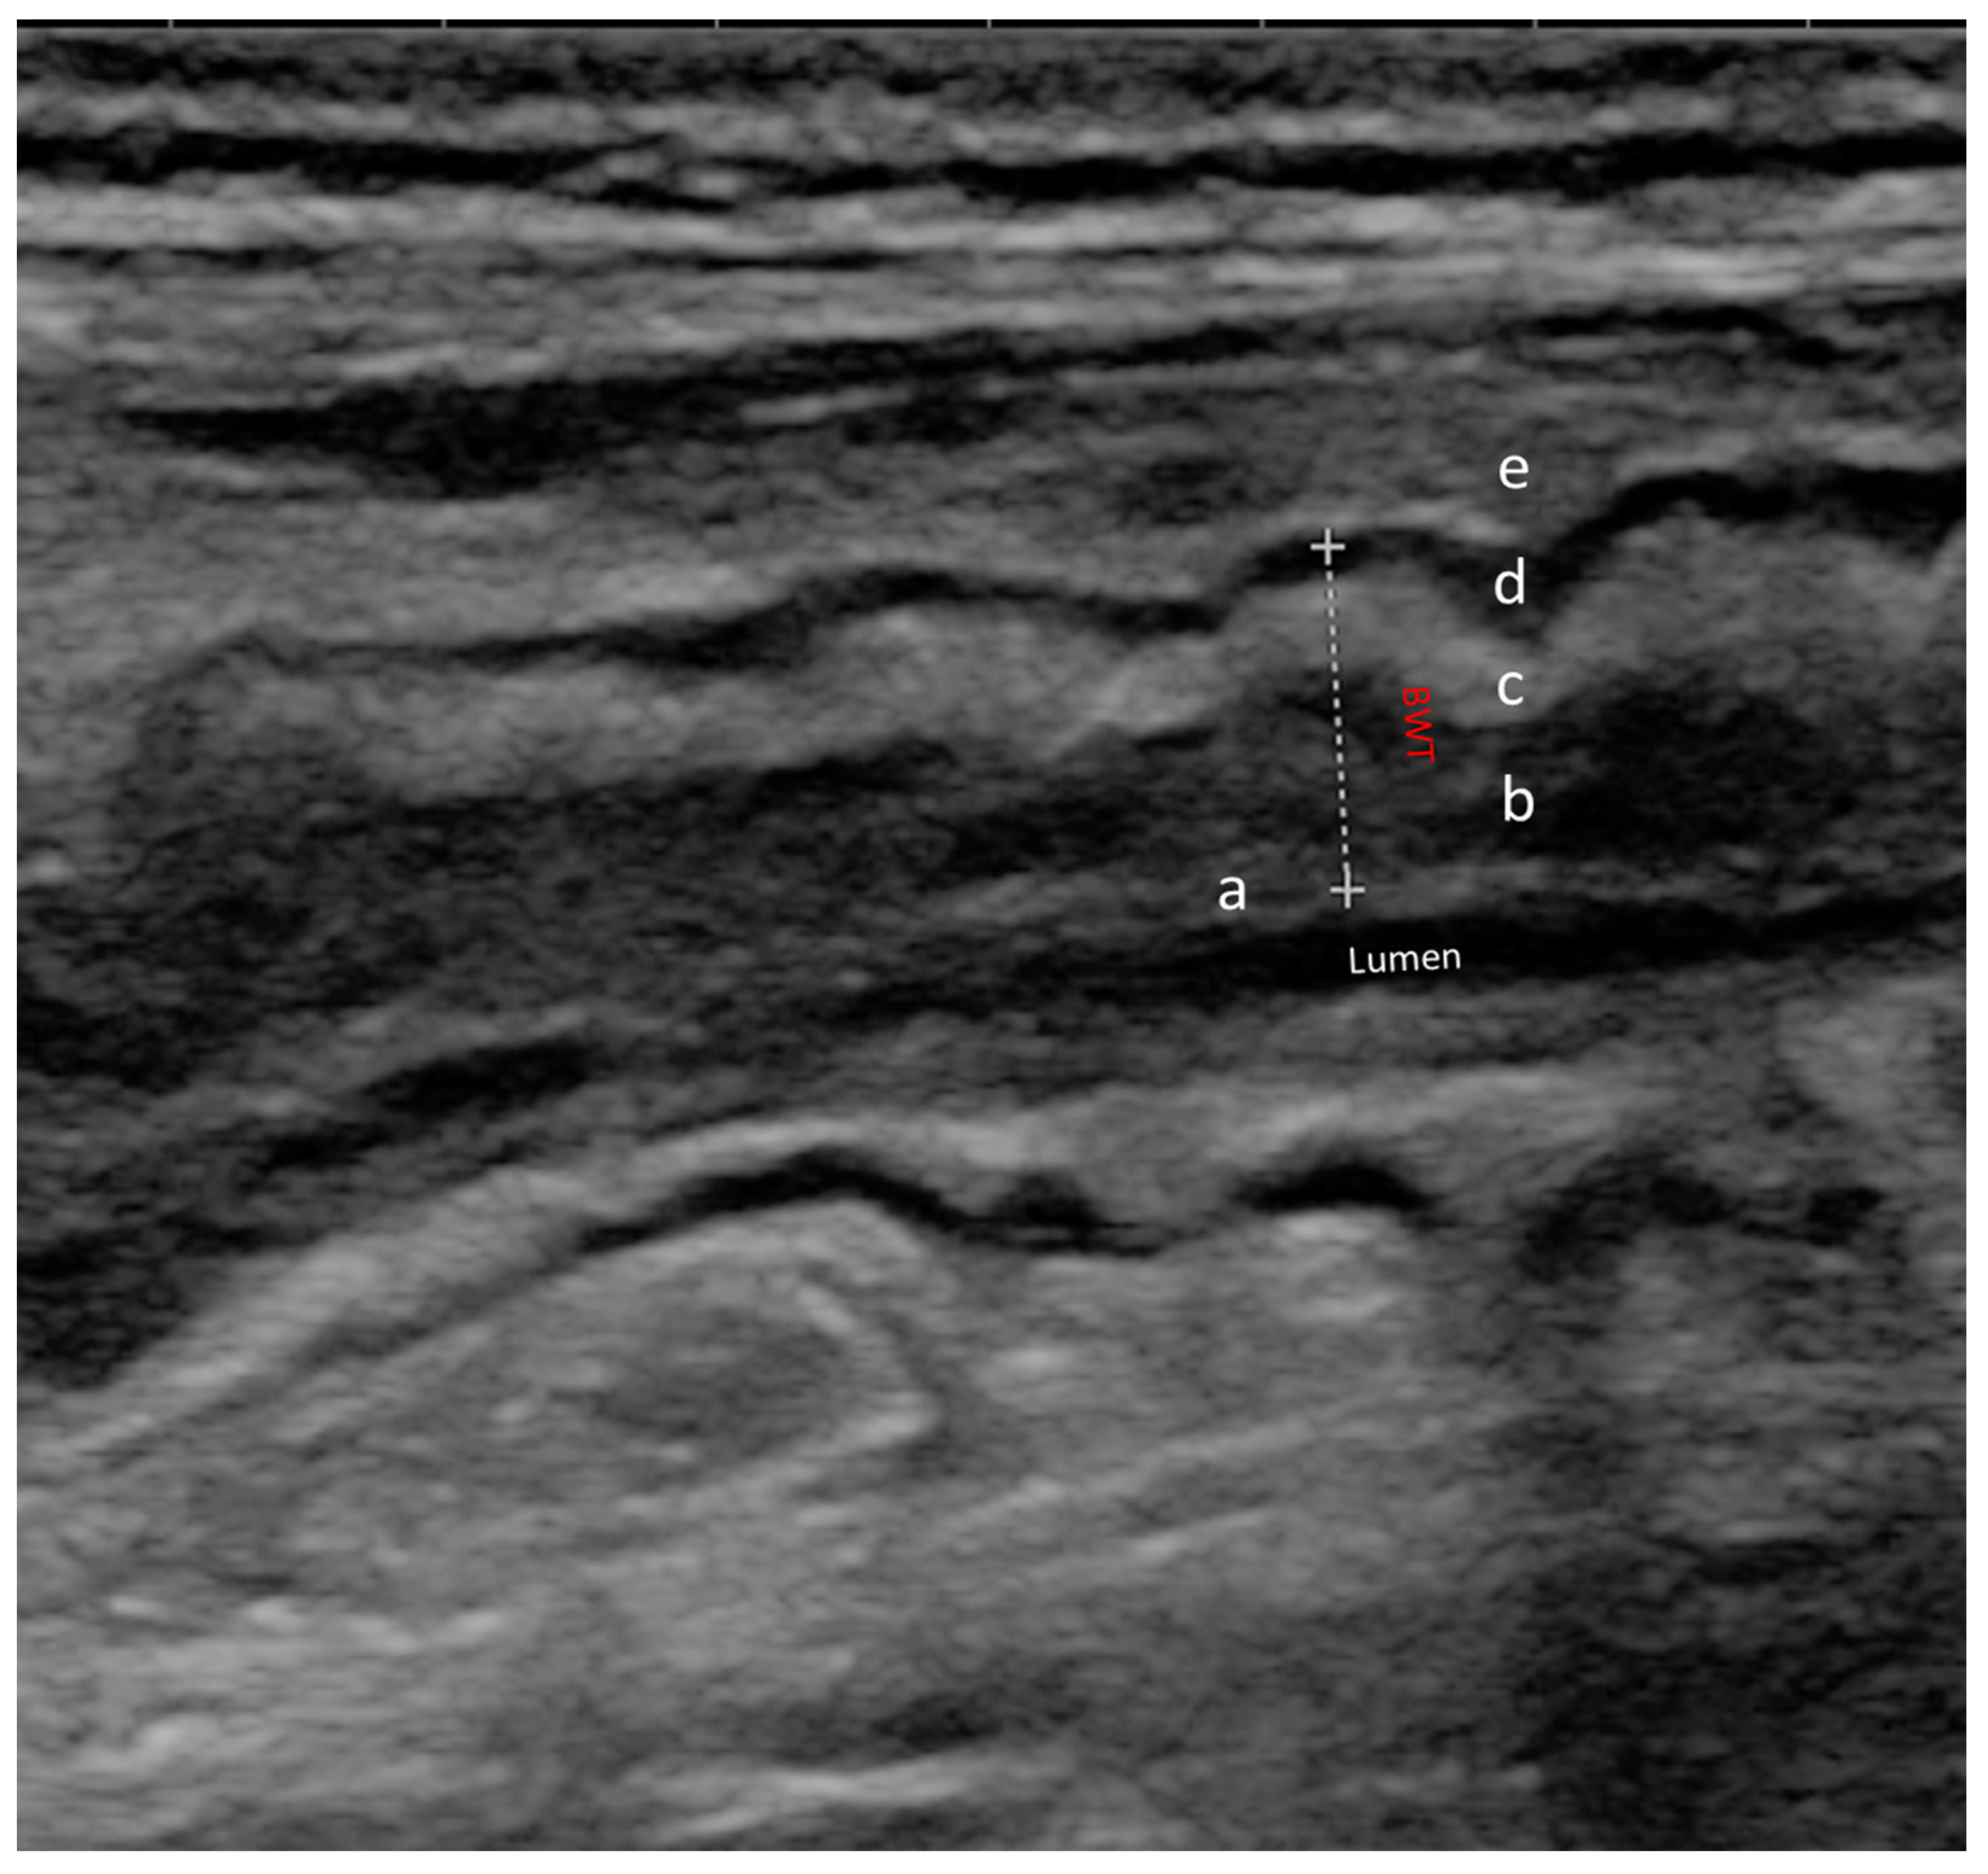

- Calabrese, E.; Maaser, C.; Zorzi, F.; Kannengiesser, K.; Hanauer, S.B.; Bruining, D.H.; Iacucci, M.; Maconi, G.; Novak, K.L.; Panaccione, R.; et al. Bowel Ultrasonography in the Management of Crohn’s Disease. A Review with Recommendations of an International Panel of Experts. Inflamm. Bowel Dis. 2016, 22, 1168–1183. [Google Scholar] [CrossRef] [PubMed]

- Kucharzik, T.; Tielbeek, J.; Carter, D.; Taylor, S.A.; Tolan, D.; Wilkens, R.; Bryant, R.V.; Hoeffel, C.; De Kock, I.; Maaser, C.; et al. ECCO-ESGAR Topical Review on Optimizing Reporting for Cross-Sectional Imaging in Inflammatory Bowel Disease. J. Crohns Colitis 2022, 16, 523–543. [Google Scholar] [CrossRef]

- Ilvemark, J.F.K.F.; Hansen, T.; Goodsall, T.M.; Seidelin, J.B.; Al-Farhan, H.; Allocca, M.; Begun, J.; Bryant, R.V.; Carter, D.; Christensen, B.; et al. Defining Transabdominal Intestinal Ultrasound Treatment Response and Remission in Inflammatory Bowel Disease: Systematic Review and Expert Consensus Statement. J. Crohns Colitis 2022, 16, 554–580. [Google Scholar] [CrossRef] [PubMed]

- Novak, K.L.; Nylund, K.; Maaser, C.; Petersen, F.; Kucharzik, T.; Lu, C.; Allocca, M.; Maconi, G.; de Voogd, F.; Christensen, B.; et al. Expert Consensus on Optimal Acquisition and Development of the International Bowel Ultrasound Segmental Activity Score [IBUS-SAS]: A Reliability and Inter-rater Variability Study on Intestinal Ultrasonography in Crohn’s Disease. J. Crohns Colitis 2021, 15, 609–616. [Google Scholar] [CrossRef] [PubMed]

- Sævik, F.; Eriksen, R.; Eide, G.E.; Gilja, O.H.; Nylund, K. Development and Validation of a Simple Ultrasound Activity Score for Crohn’s Disease. J. Crohns Colitis 2021, 15, 115–124. [Google Scholar] [CrossRef] [PubMed]